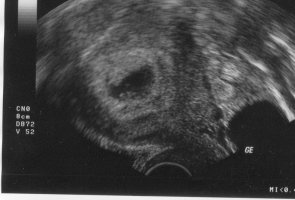

Naja, dafür werde ich Freitag früh mit meinem ersten richtigen FA Termin (dem planmäßigen belohnt) und hoffe dann schon das Herzchen schlagen zu sehen.